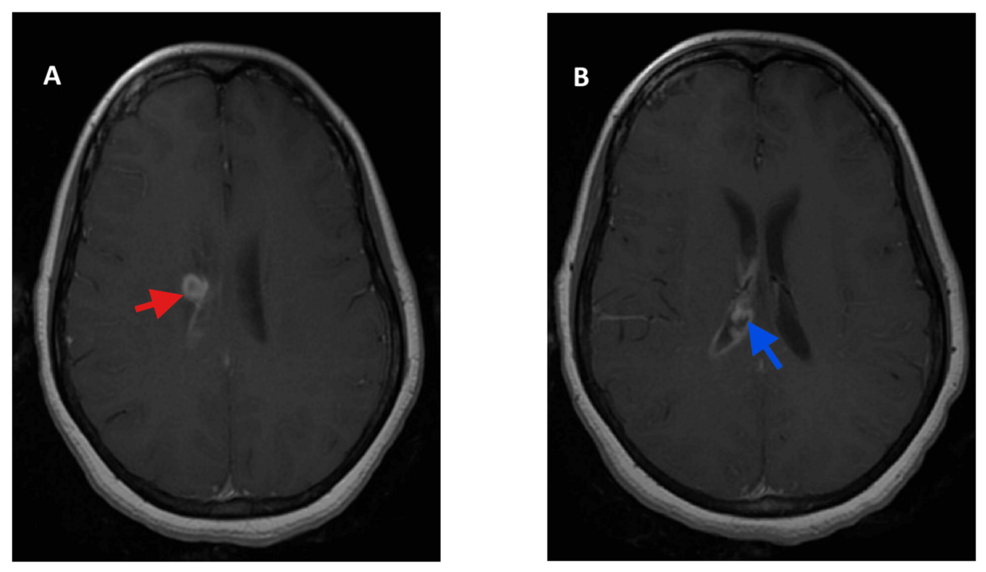

The patient presented with a week-long history of headache, fever, and altered mental status. Initial diagnostic imaging revealed a ring-enhancing lesion in the brain, concerning for an abscess. Further investigation confirmed the presence of Aggregatibacter aphrophilus both in the abscess and within the cerebrospinal fluid, indicating ventriculitis – inflammation of the brain’s ventricles. This combination of infection is exceptionally uncommon, making this case particularly noteworthy for the medical community.

Diagnosing a brain abscess can be challenging, as symptoms – headache, fever, neurological deficits – can mimic other, more common conditions. Neuroimaging, such as MRI or CT scans, is essential for identifying the presence of an abscess. However, identifying the causative organism requires analysis of the abscess material or cerebrospinal fluid. In this instance, standard bacterial cultures initially failed to identify the Aggregatibacter aphrophilus, requiring specialized testing and prolonged incubation periods.

The patient underwent surgical drainage of the abscess, followed by a prolonged course of intravenous antibiotics tailored to the identified bacterium. She similarly received supportive care to manage the inflammation and neurological symptoms. The case report details the specific antibiotic regimen used and the patient’s response to treatment. While the initial prognosis was guarded, the patient ultimately demonstrated significant clinical improvement and was discharged with continued antibiotic therapy and close neurological follow-up.

The Role of Ventriculitis in Complicating the Case